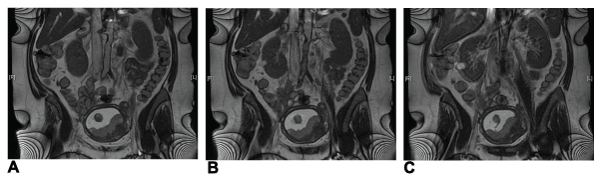

Duplex ultrasound showed monophasic flow profile in both common femoral arteries. Following magnetic resonance tomography which showed a complete obstruction of the iliac artery on the left side and a high-grade stenosis of the common iliac artery on the right side (Figure 1).

Figure 1: Magnetic resonance tomography prior to operation. The uterus and fetus is shown in the lower part of the abdomen. Pictures A to C are serial. A:

shows the beginning of the occlusion of the left common iliac artery. B: shows a high-grade stenosis of the right common iliac artery and again the occlusion of

the left one, additionally severe calcifications of the infrarenal aorta. C: shows that the right external iliac artery is open and that the left one is still occluded.